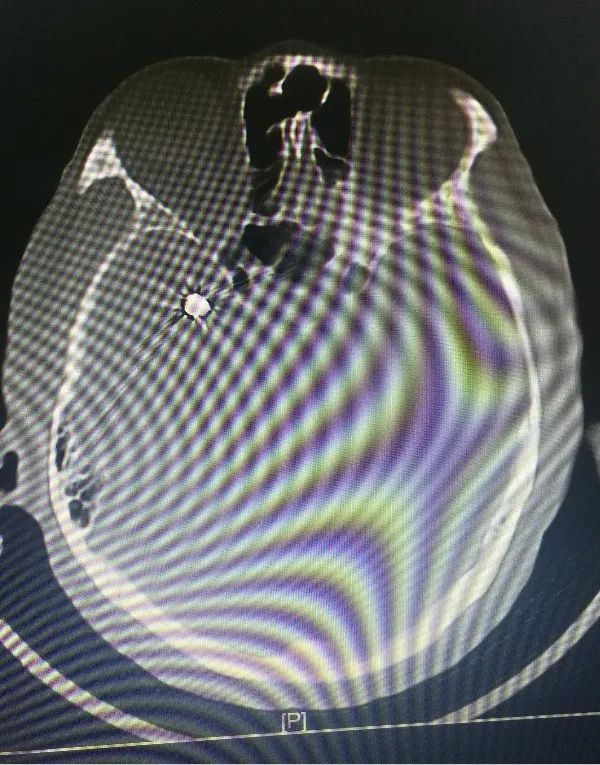

近日,省人民醫(yī)院神經(jīng)外科為一位高齡動脈瘤患者施行了介入治療,成功栓塞了破裂的大腦中動脈瘤?;颊咭蛲话l(fā)暈厥后頭痛不適入院,急診行顱腦CT檢查提示蛛網(wǎng)膜下腔出血,行顱腦CTA檢查后證實患者存在右側(cè)大腦中動脈瘤?;颊吒啐g,既往基礎(chǔ)病多,高血壓病、糖尿病、冠心病、雙側(cè)頸動脈硬化、雙側(cè)腹股溝疝術(shù)后等,手術(shù)風(fēng)險較大,經(jīng)家屬簽字同意后,當(dāng)日急診全麻下行“右側(cè)大腦中動脈瘤介入栓塞術(shù)”,術(shù)中見血管迂曲明顯,導(dǎo)管到位艱難,經(jīng)過努力,手術(shù)順利結(jié)束。術(shù)后予多次腰椎穿刺術(shù)釋放血性腦脊液,患者頭痛頭暈癥狀漸緩解?;颊咦≡褐委?/span>10天后順利康復(fù)出院,未留后遺癥。